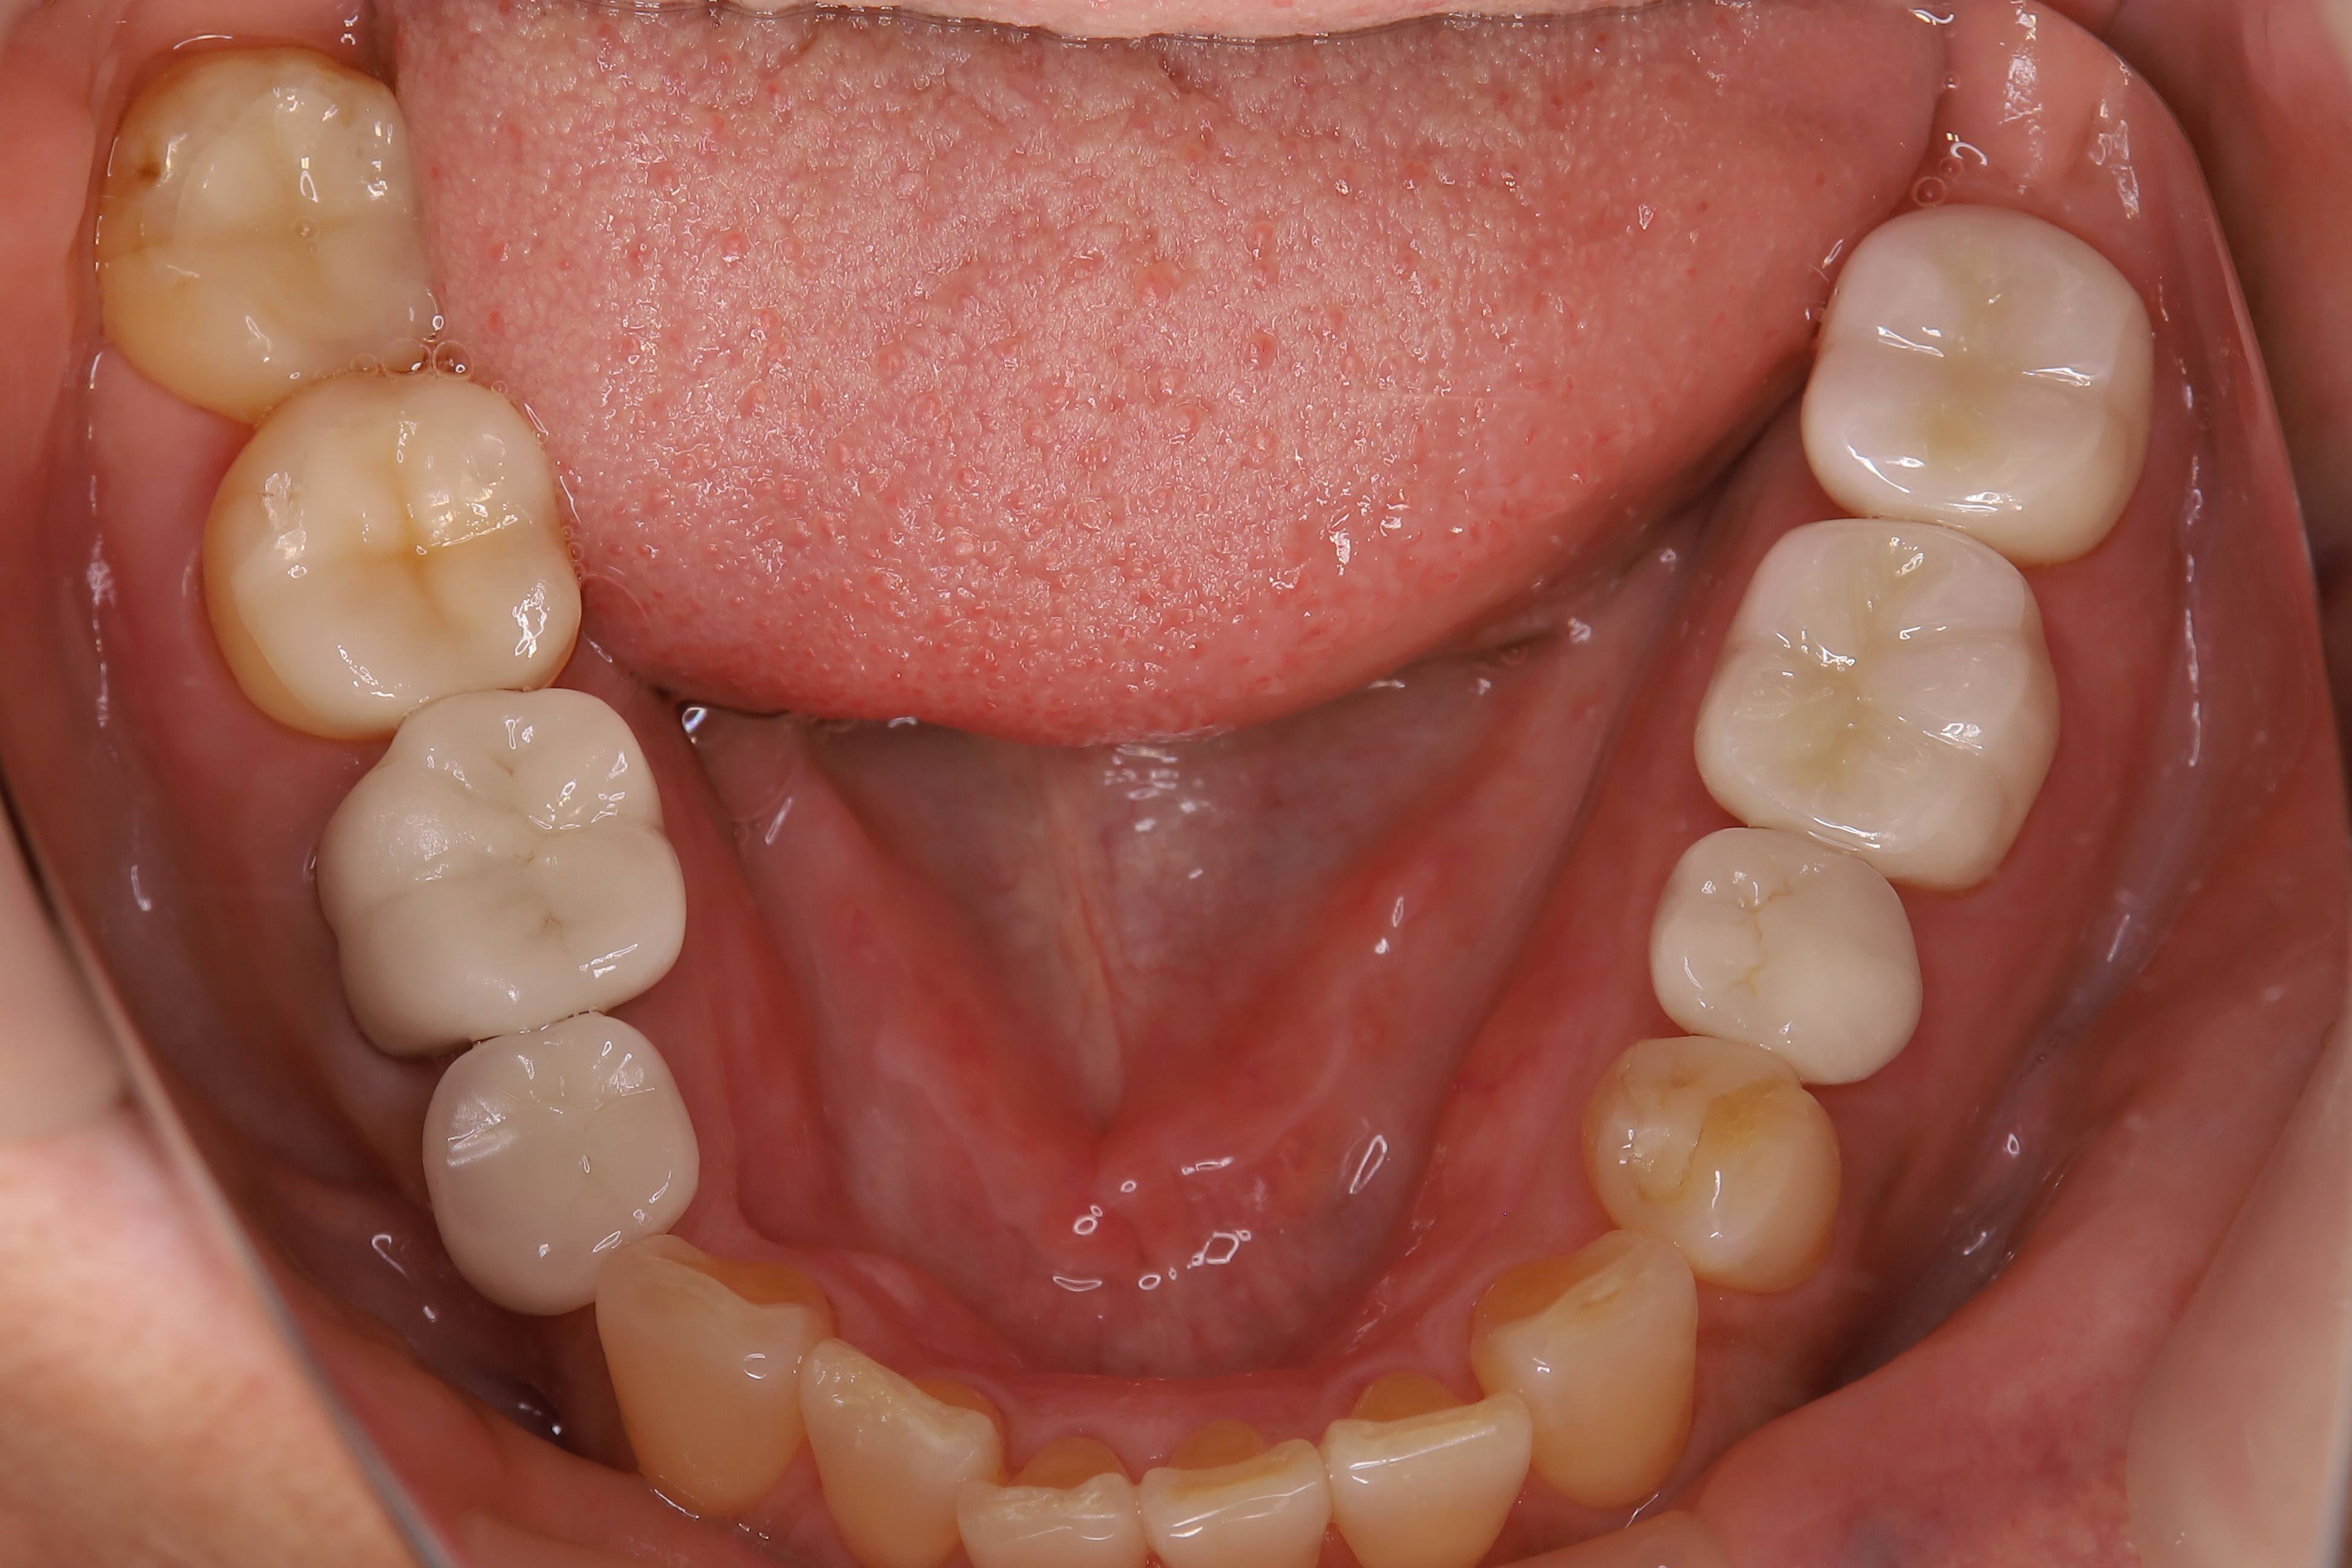

審美歯科治療

症例紹介